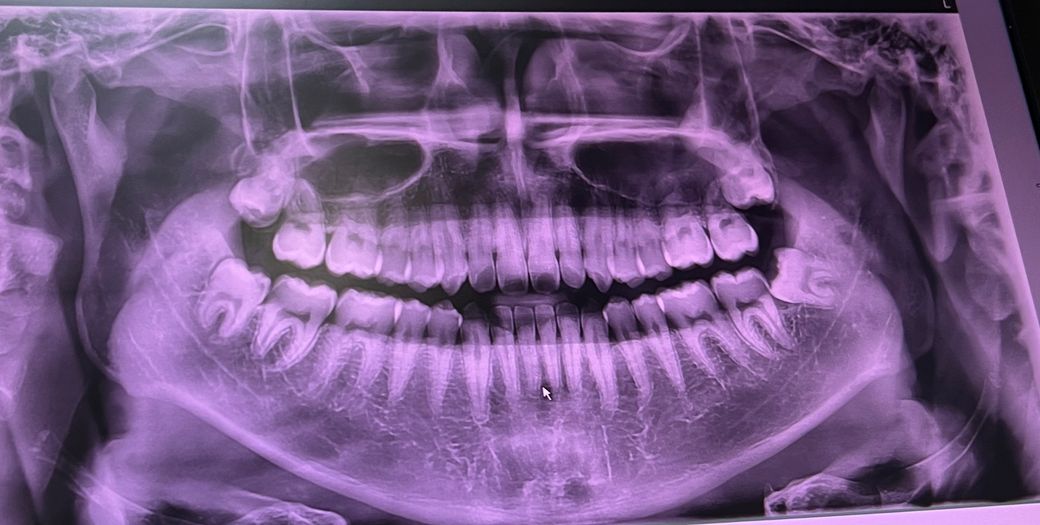

가만히 있어도 아랫니가 시려서 치과에 갔더니 치석때문일 수도 있다고 스케일링 하고 경과 지켜보자고 하십니다.

그리고 충치가 여러군데 있다고 하셨고 사랑니에도 있어서 사랑니 뽑아야 된다고 하시더라구요.

사랑니 한개는 신경에 근접해 있다고 하셨습니다.

결론은 사랑니 전문 치과에 한번 가봐야 할까요?

아니면 기존 치과에서 뽑아도 될까요?

거기 치과에서 뺄 수 없다고 판단되면 큰 치과가라고 보냅니다 별말 없었으면 발치 충분히 가능한 겁니다

다만 전문병원 간다고 뾰족한 수가 있는건 아닙니다 빼다가 신경 건드렸을때 탈날 가능성 있는건 누가 뽑아도 마찬가지입니다

그래도 ct찍고 위치 관계확인 후 최대한 조심할 필요는 있죠